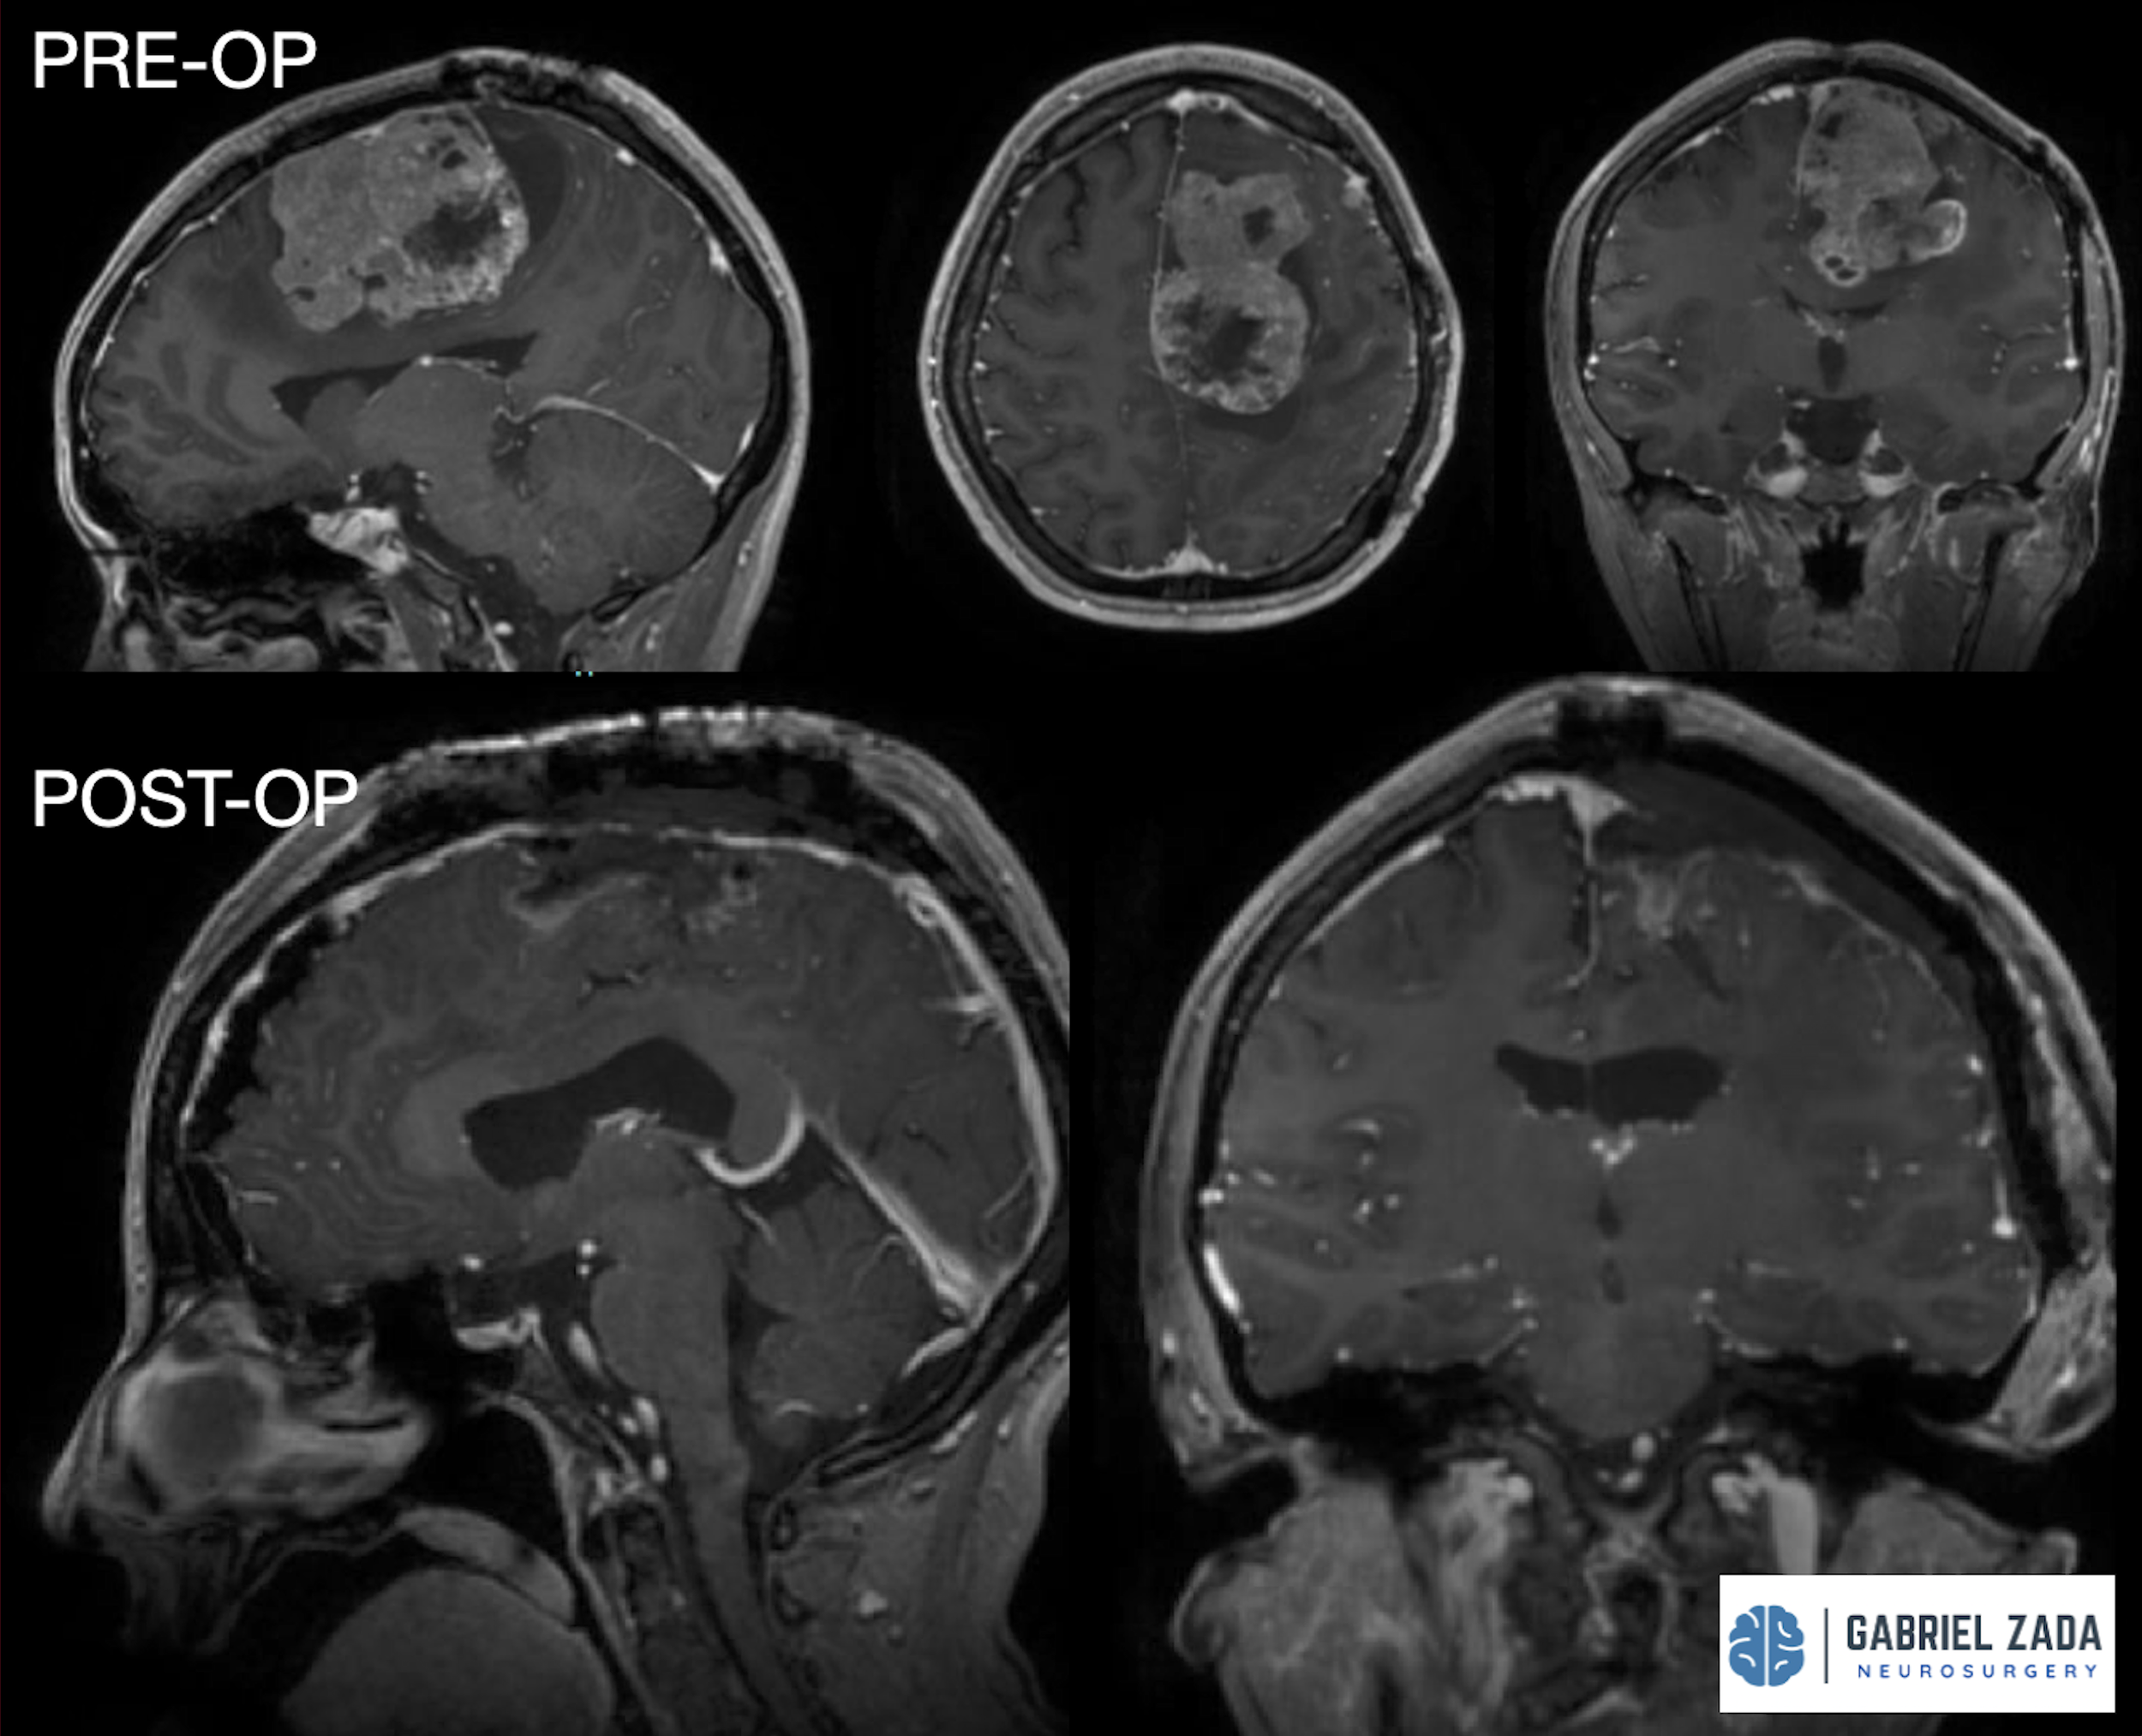

Explore this comprehensive gallery featuring pre‑ and post‑operative imaging of patients with skull‑base tumors treated by Gabriel Zada, MD, MS, FAANS, FACS. These cases highlight Dr. Zada’s expertise in advanced neurosurgical techniques and outcomes.

*Representative cases shown for educational purposes. All images de-identified. Individual results vary.